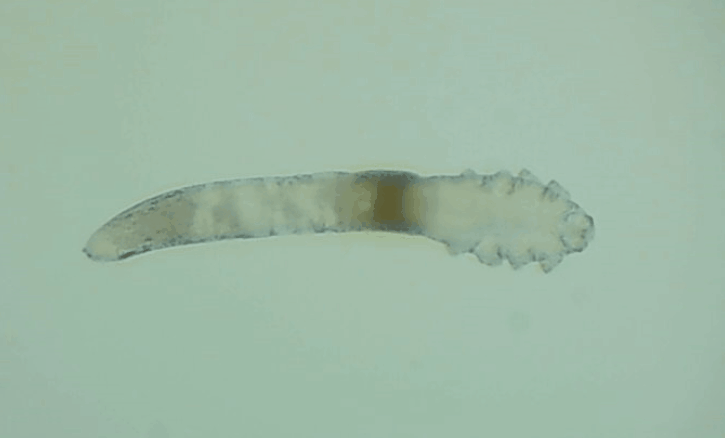

是的, 眼睛也會(huì)有蟲子,那就是蠕形螨。眼睛發(fā)紅、干癢、疲勞、睫毛脫落,這些都是因?yàn)樗?/div>

其實(shí)蠕形螨主要活動(dòng)在毛囊和皮脂腺中,以皮膚碎屑和腺體分泌物作為食物來源,而睫毛根部的瞼板腺是排泄油脂的重要部位,因此眼睫毛和瞼板腺也是螨蟲的主要活動(dòng)場(chǎng)所。

一般來說,15天內(nèi),一只蠕形螨會(huì)在你眼睛里產(chǎn)下50只蟲卵。如果不及時(shí)除螨,它們會(huì)迅速繁殖,從而導(dǎo)致睫毛脫落、亂生、眼睛紅癢,甚至引發(fā)眼部炎癥。如果影響到角膜,就會(huì)造成視力下降甚至失明。

在廈門眼科中心檢查后發(fā)現(xiàn),在她的眼睛上竟然有大量的螨蟲,僅是檢查用的2、3根睫毛上就有8只,除螨蟲外,她的眼睛還出現(xiàn)了瞼緣炎以及干眼癥。